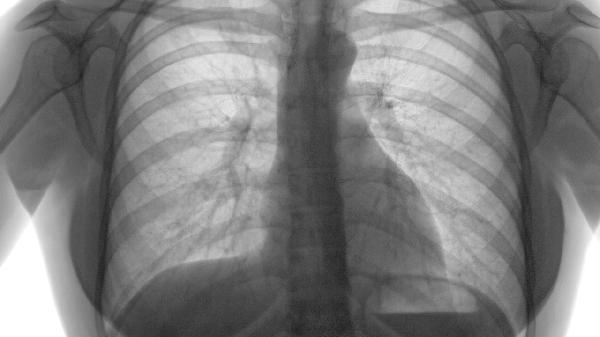

肺气肿不会传染人。肺气肿是一种慢性阻塞性肺疾病,主要由长期吸烟、空气污染、遗传因素、反复呼吸道感染以及职业性粉尘暴露等因素引起。

肺气肿症状主要表现为早期活动后气短、进展期持续性呼吸困难、终末期呼吸衰竭伴并发症。 1、早期表现: 轻度活动后气...

肺气肿常见症状包括气短、慢性咳嗽、胸闷、乏力等,病情发展可能出现桶状胸、体重下降等体征。 1、气短 早期表现为活...